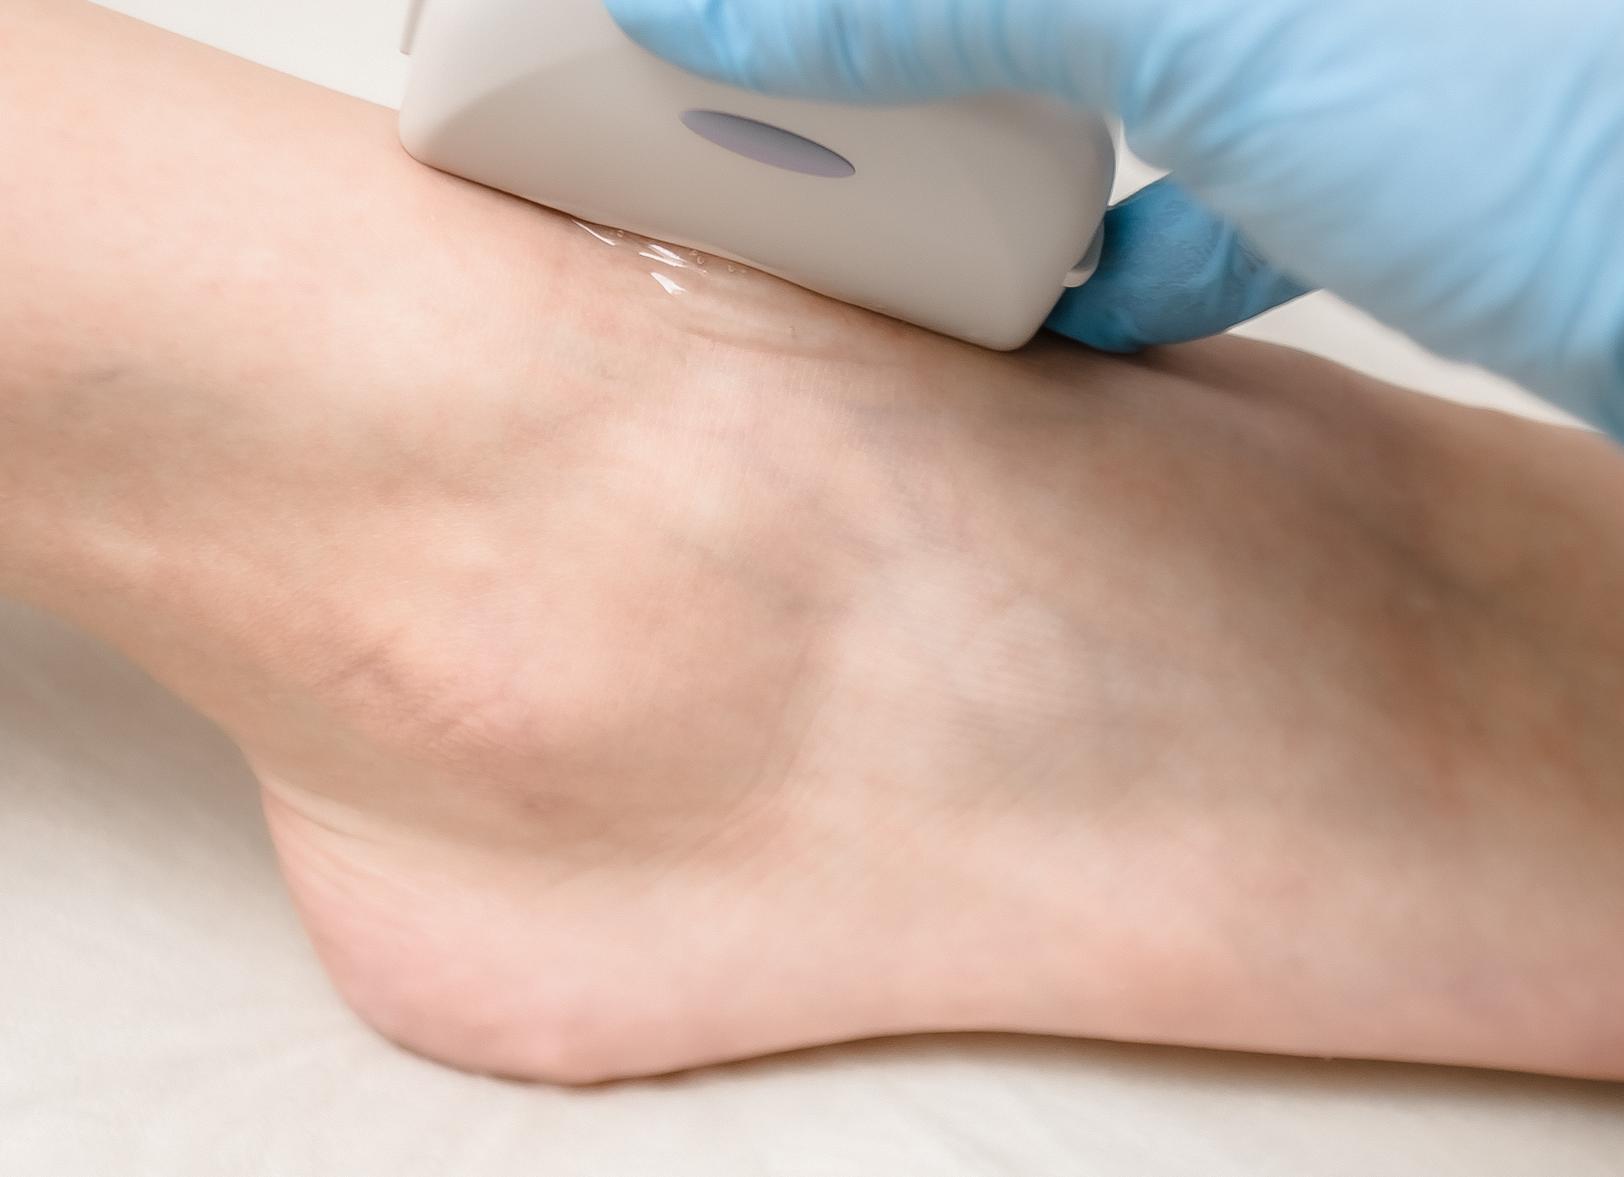

УЗИ сочленения не обладает противопоказаниями и не нуждается в наличии предварительной подготовки. Всю продолжительность сеанса человек может пребывать в лежачей или же сидячей позе. Специалист, проводящий УЗИ, наносит на голеностопную зону небольшое количество геля, дабы устранить помехи, вызванные попадание воздуха под датчик. Как правило, голеностоп рассматривают в 4 проекциях:

Во время процедуры пациент находится в положении сидя или лежа на кушетке. На ступню наносится специальный гель для отражения ультразвуковых волн и лучшего контакта датчика с кожей. Наличие геля помогает устранить создание помех в показаниях ультразвукового аппарата, которые создает воздух. Исследование стопы осуществляется в 4 разных проекциях:

Для того чтобы ультразвуковые волны хорошо распространялись по тканям сустава, необходимо исключить возможность образования воздушной прослойки между исследуемой тканью и сканером. Для этого используются специальные гели.